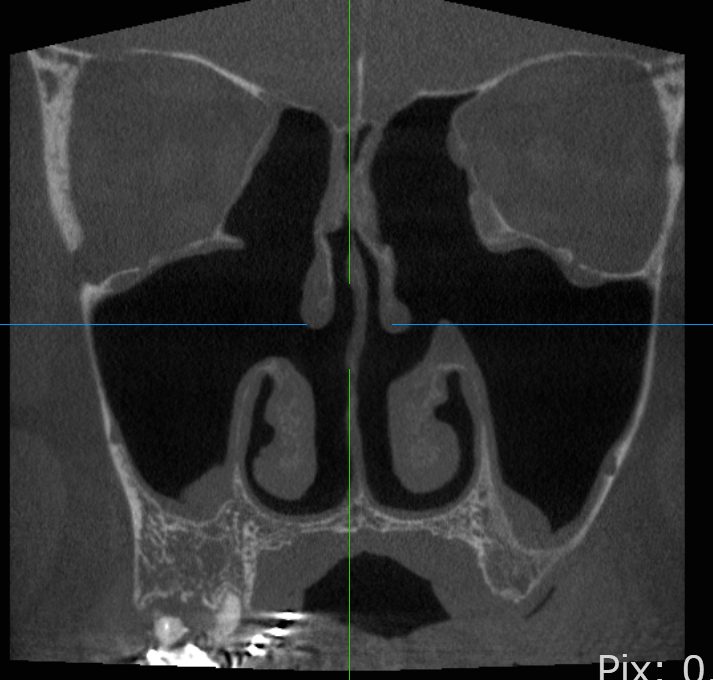

鼻中隔湾曲症の症例紹介

鼻中隔の著しい右偏位に対し、内視鏡下で偏位部分の軟骨と骨を切除・調整。

その結果、鼻中隔は正中に整復され、鼻腔の通気性が大きく改善しています。

鼻中隔が右側(画面左)に大きく曲がっており、右鼻腔が狭くなっていました。鼻中隔の著しい弯曲に対し、内視鏡下で矯正を行いました。左右の通気が改善し、機能的にも良好な結果が得られました。